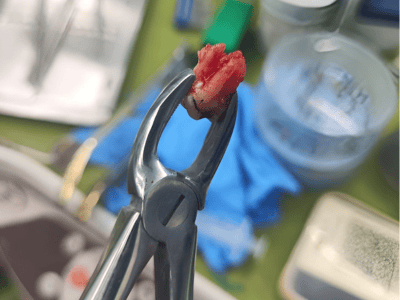

provides expert treatment for gum diseases, receding gums, and dental implant procedures using the

the best possible care for every patient. Whether you need routine checkups or complex periodontal

From routine checkups to complex gum treatments, dental implants, laser dentistry, root canal treatments (RCT), and smile